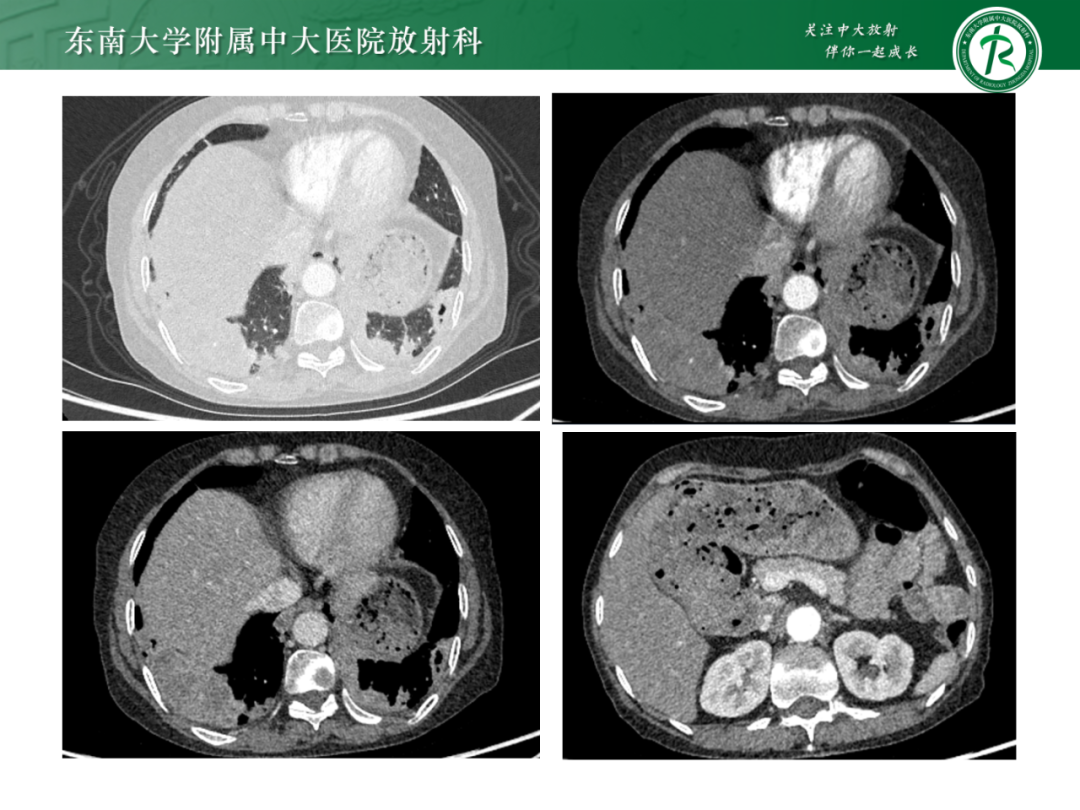

肺多发空洞病例分析|今日病例

作者:东南大学附属中大医院 吕文晖

来源:东南大学附属中大医院放射科